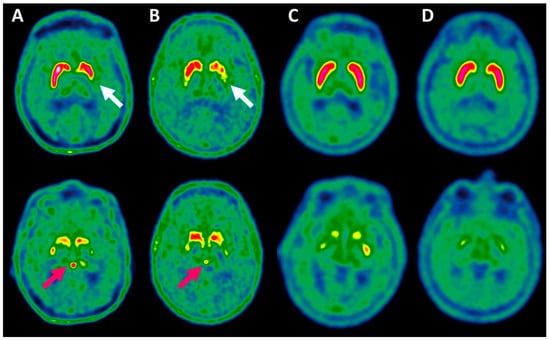

2.1. Evaluation of Basal Ganglia 18F-DOPA Uptake by Visual Assessment and Automated Method to Identify NSD

2.2. Evaluation of Pineal Body 18F-DOPA Uptake Parameters to Identify NSD